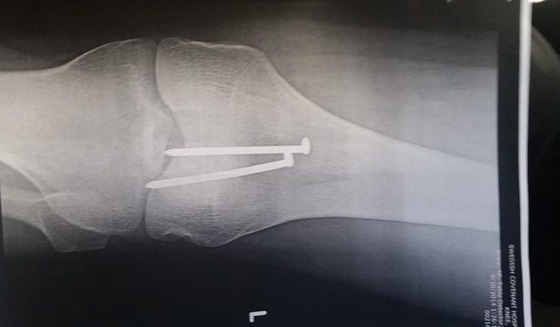

نجا نجار متدرب بأعجوبة من إصابة مروعة بعدما صوب مسدس مسامير في اتجاه ركبته. وقضى الشاب يومه الثاني من التدريب في تأطير الأخشاب داخل موقع بناء في شيكاغو عندما ضغط على خرطوم الغاز المتصل بالمسدس، حيث اهتز بشدة وبدأ بإطلاق المسامير على ركبته. بعد وقوع الحادث، قام مجموعة من زملائه بنقله إلى المستشفى، وأبلغه الأطباء في وقت لاحق أنه نجا بأعجوبة من الحادث، فقد كادت المسامير أن تقطع الشريان الرئيسي في الفخذ. وقال الأطباء إن 6 جراحين أجروا عملية جراحية خطيرة للشاب، ووصفوها بأنها معجزة طبية بعد أن عجزت الأدوية على زحزحة المسامير.